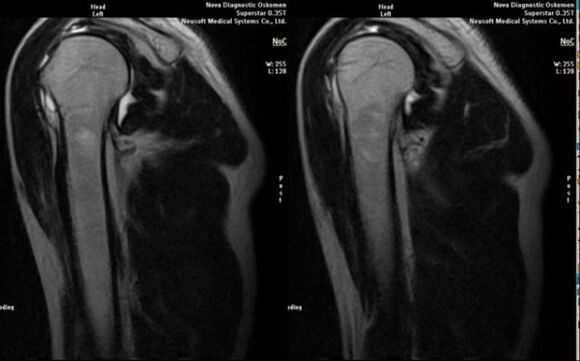

- erresonantzia magnetikoa eta ordenagailu bidezko tomografia;

Artrosiaren garapena zuzenean adierazten duten seinaleen artean artikulazio-espazioaren murrizketa nabarmena agertzea, subcartilaginous-egituren esklerosia, kondrozitoen geruza bera mehetzea, osteofitoen agerpena eta artikulazio barneko likidoan gatz-kristalak jartzea daude.